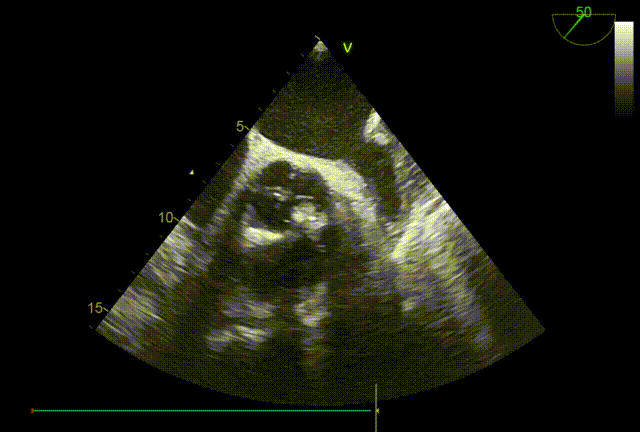

26VenusAplus+snare

瓣膜内22mm球囊后扩张,左冠无显影

LM烟囱支架植入4.0*30mm